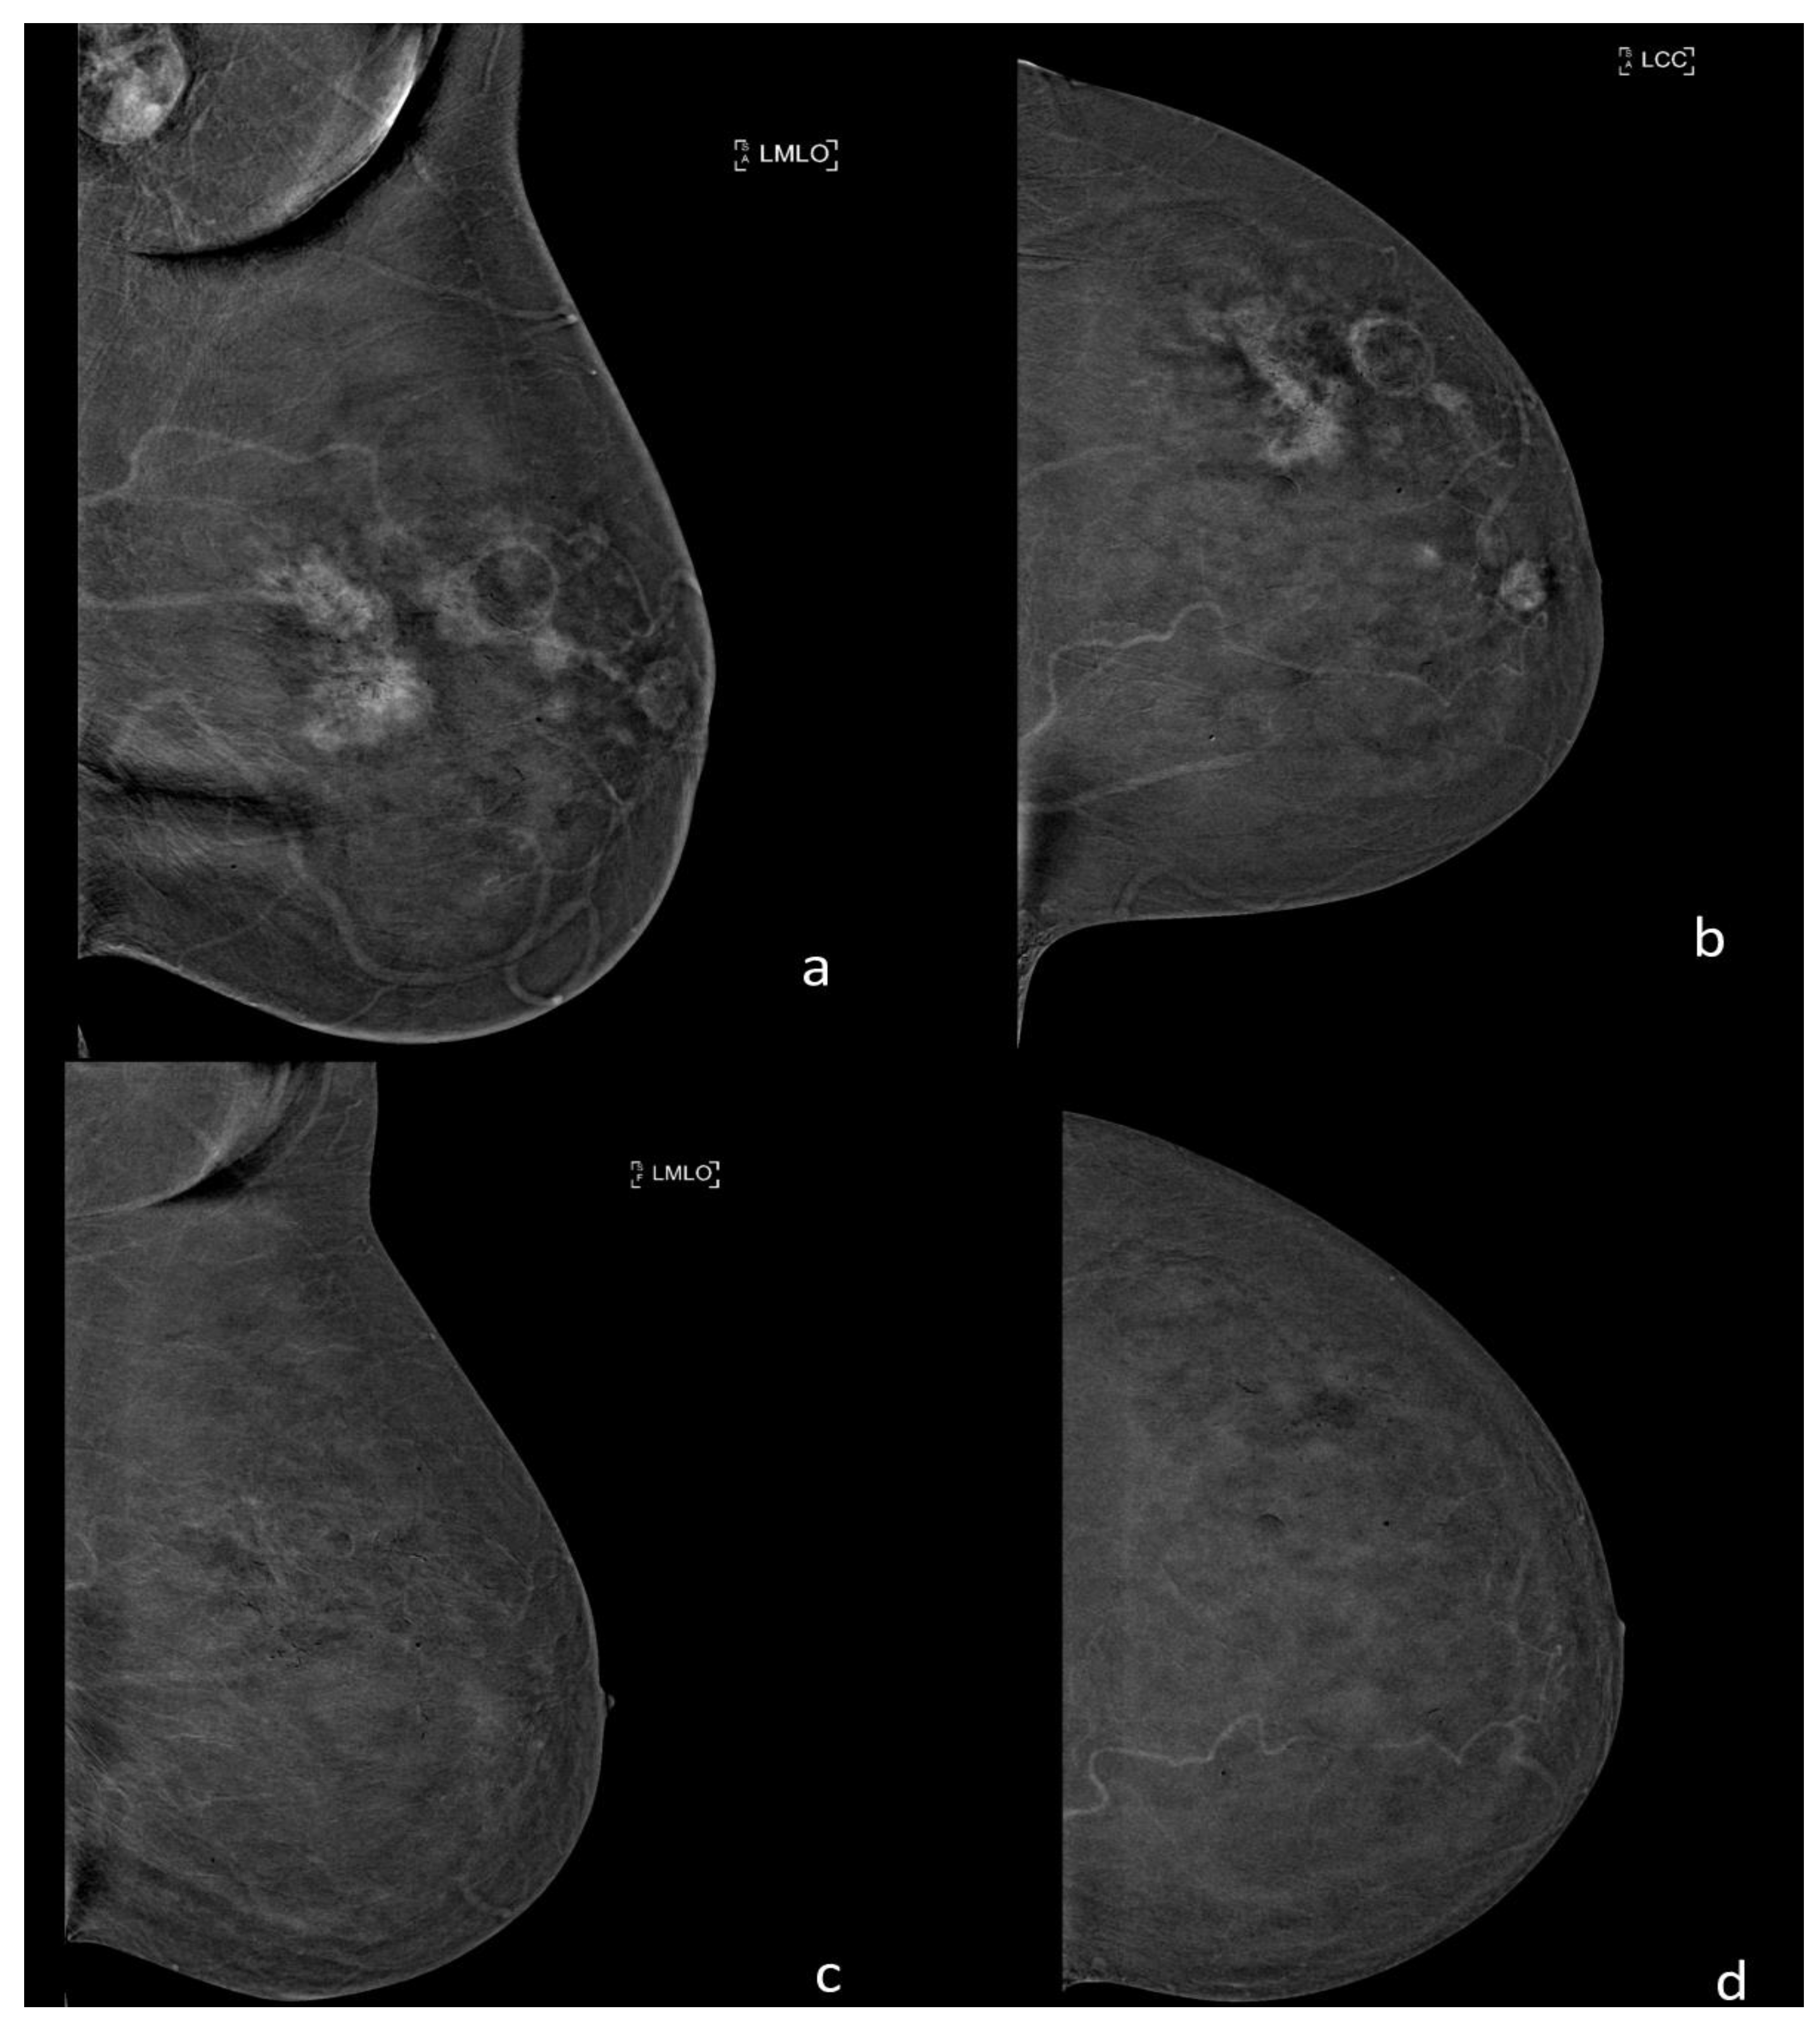

10. Contrast Enhanced Mammography (CEM)

- Bicchierai, G.; Amato, F.; Vanzi, B.; De Benedetto, D.; Boeri, C.; Vanzi, E.; Di Naro, F.; Bianchi, S.; Cirone, D.; Cozzi, D.; et al. Which clinical, radiological, histological, and molecular parameters are associated with the absence of enhancement of known breast cancers with Contrast Enhanced Digital Mammography (CEDM)? Breast 2020, 54, 15–24. [Google Scholar] [CrossRef]

- Zanardo, M.; Cozzi, A.; Trimboli, R.M.; Labaj, O.; Monti, C.B.; Schiaffino, S.; Carbonaro, L.A.; Sardanelli, F. Technique, protocols and adverse reactions for contrast-enhanced spectral mammography (CESM): A systematic review. Insights Imaging 2019, 10, 76. [Google Scholar] [CrossRef] [PubMed]

- Jochelson, M.S.; Dershaw, D.D.; Sung, J.S.; Heerdt, A.S.; Thornton, C.; Moskowitz, C.S.; Ferrara, J.; Morris, E.A. Bilateral contrast-enhanced dual-energy digital mammography: Feasibility and comparison with conventional digital mammography and MR imaging in women with known breast carcinoma. Radiology 2013, 266, 743–751. [Google Scholar] [CrossRef]

- Łuczyńska, E.; Heinze-Paluchowska, S.; Hendrick, E.; Dyczek, S.; Ryś, J.; Herman, K.; Blecharz, P.; Jakubowicz, J. Comparison between breast MRI and contrast-enhanced spectral mammography. Med. Sci. Monit. 2015, 21, 1358–1367. [Google Scholar] [CrossRef] [PubMed]

- Fallenberg, E.M.; Schmitzberger, F.F.; Amer, H.; Ingold-Heppner, B.; Balleyguier, C.; Diekmann, F.; Engelken, F.; Mann, R.M.; Renz, D.M.; Bick, U.; et al. Contrast-enhanced spectral mammography vs. mammography and MRI-clinical performance in a multi-reader evaluation. Eur. Radiol. 2017, 27, 2752–2764. [Google Scholar] [CrossRef]

- Ghaderi, K.F.; Phillips, J.; Perry, H.; Lotfi, P.; Mehta, T.S. Contrast-enhanced Mammography: Current Applications and Future Directions. Radiographics 2019, 39, 1907–1920. [Google Scholar] [CrossRef] [PubMed]

- Amato, F.; Bicchierai, G.; Cirone, D.; Depretto, C.; Di Naro, F.; Vanzi, E.; Scaperrotta, G.; Bartolotta, T.V.; Miele, V.; Nori, J. Preoperative locoregional staging of invasive lobular carcinoma with contrast-enhanced digital mammography (CEDM). Radiol. Med. 2019, 124, 1229–1237. [Google Scholar] [CrossRef] [PubMed]

- Bicchierai, G.; Tonelli, P.; Piacenti, A.; De Benedetto, D.; Boeri, C.; Vanzi, E.; Bianchi, S.; Cirone, D.; Kaur Gill, M.; Miele, V.; et al. Evaluation of contrast-enhanced digital mammography (CEDM) in the preoperative staging of breast cancer: Large-scale single-center experience. Breast, J. 2020, 26, 1276–1283. [Google Scholar] [CrossRef] [PubMed]